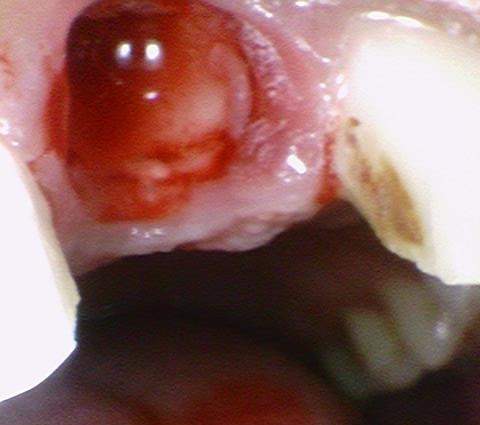

발치해서 보니 위와 같이 잇몸 깊은 곳까지 두동강 나 있어서

살리기 힘든 상태였습니다.

발치를 하였고 치아를 빼면 구멍이 생기니

잇몸이 아무는데까지 기다렸다가 브릿지를 해야 합니다.